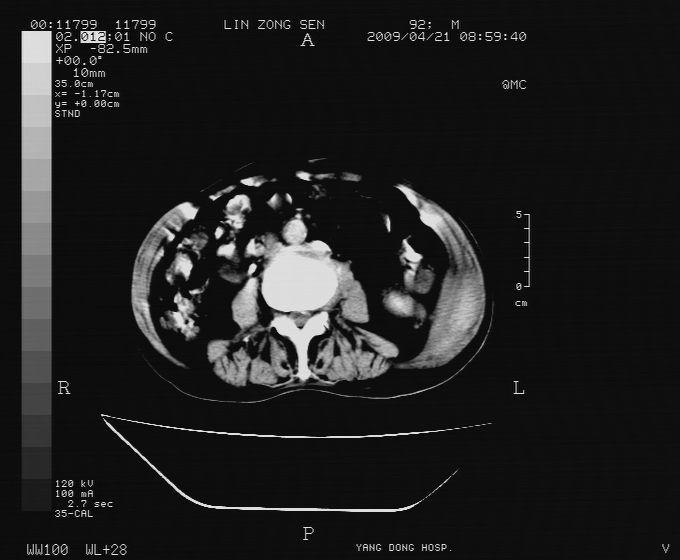

以下是引用卜一在2009-4-22 4:08:00的发言:[br]右肾积水伴输尿管上段积水!左侧肾多发囊肿!左侧腹壁软组织增厚,层次模糊,内密度较高—不排除血管瘤伴出血!